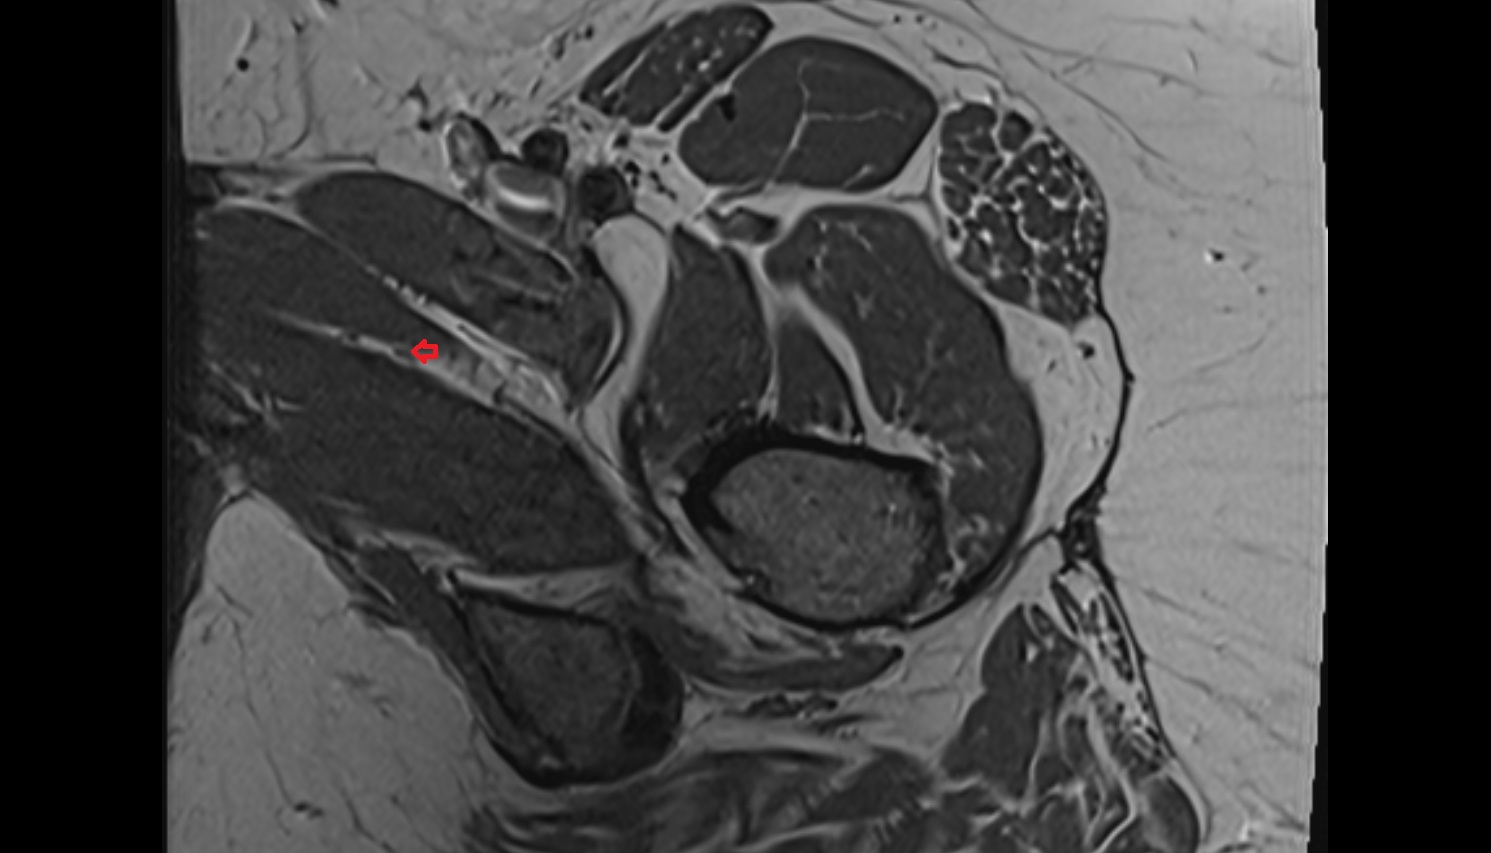

- Heart

- Left ventricle

- Right atrium

- Left atrium

- Right ventricle

- Interventricular Septum

- Left atrioventricular valve (mitral or bicuspid valve)

- Right atrioventricular valve (tricuspid valve)